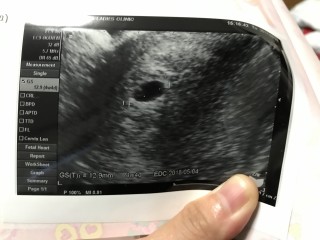

二人目です。 まだ少し早かったらしく、「おそらく、子宮内妊娠だろう」としか言われず。 GSらしいやつは、3.4mmでした。

4週と4日目。 12.9㎜でした。 楽しみっ!